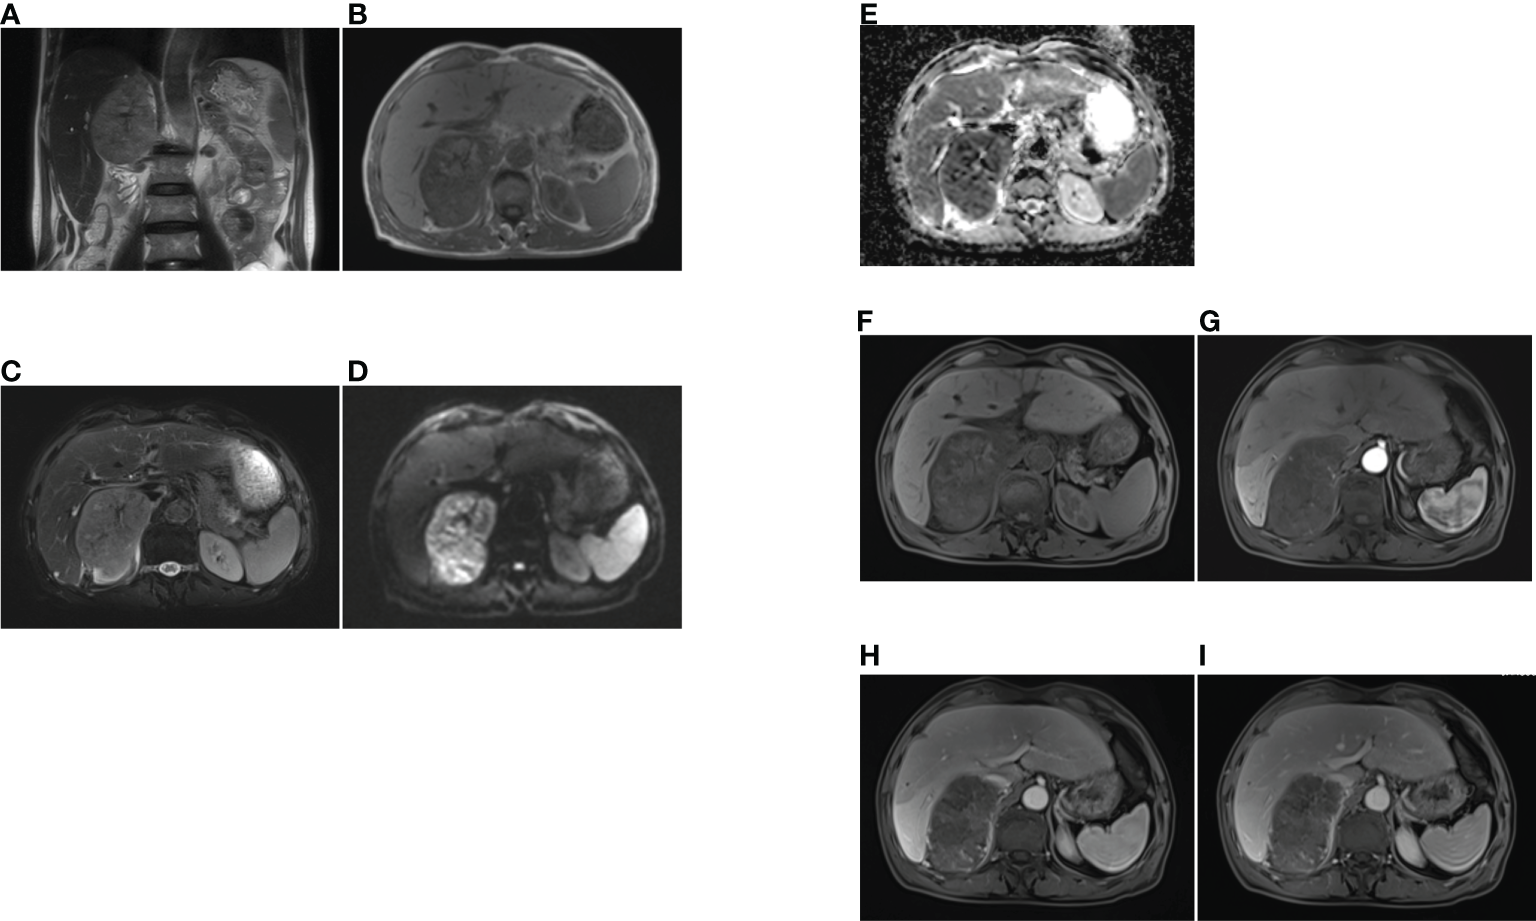

Figure 2 The MRI findings of primary adrenal sarcoma. (A) coronal T2-weighted MR image, (B) axial T1-weighted MR image, (C) axial fat suppression T2-weighted MR image, (D, E) The tumor showed heterogeneous high signal intensity on DWI and low signal intensity on ADC map, (F–I) axial fat suppression T1-weighted MR imaging (F), and Gadolinium-enhanced T1-weighted MR mages at arterial (G), portal (H) and delayed phases (I), the tumor exhibited heterogeneous enhancement and no enhancement in the central scar.

A 69-year-old man with an incidental right adrenal gland mass was admitted to our institution. He had no relevant past medical history, and no family history was identified. Hematological examination did not reveal any abnormal findings. Adrenal function laboratory assay indices were normal, including cortisol, catecholamine and aldosterone. Initial CT scan revealed a round-like, well-defined slightly hypodense lesion in the right adrenal gland region measuring approximately 10.6×6.4×11.0 cm in size, with a CT value of about 34 HU. The right posterior liver, portal vein and upper pole of the right kidney were displayed (Figure 1). Right adrenal gland imaging was not conclusive. A follow-up MRI (Figure 2) revealed a 10.2×6.5×10.5 cm oval tumor in the right suprarenal region, with a high-low mixed sign on T1WI and slightly high signals on fat suppression T2WI sequence. A central scar was noted in the lesion, which was hypointense on T1WI and T2WI. Upon enhancement scan, the lesion exhibited a slight to moderate heterogeneous enhancement with no enhancement in the central scar. Visualization of the right adrenal gland was not clear. There were no significant enlarged lymphnodes or metastatic foci. Gene detection and FDG PET/CT were not carried out due to economic reasons.

For our case, the mass was detected during physical examination, without obvious clinical manifestations. In a review of previous CT imaging in 2019, no adrenal mass was found, indicating rapid progress. Reports on MRI and CT of proximal ES involving uterine body, cervix and renal have been relatively few. To date, four cases of primary adrenal epithelioid sarcoma have been reported, but imaging features were not mentioned (3–6). A typical CT of proximal ES reveals slightly lower or equal density mass in homogeneous enhancement on enhanced scan. For the larger, manifestations include tissue invasion, hemorrhage and necrosis, but it is rarely to find calcification (7). On MRI, proximal ES is usually homogeneous in signal, isointense or hyperintense in T1WI and T2WI, and homogeneous or heterogeneous enhancement, with no enhancement in the necrotic area. There is infiltration to adjacent tissues or bones in some cases (8). In our case, plain CT revealed a slightly low-density mass in the right adrenal gland. Upon MRI, the mass exhibited heterogeneous isointensity in T1WI and relative hyperintensity with hypointensity central scar inside in fat-suppression T2WI. The mass had hyperintense signals on DWI and hypointense signals on the ADC map, while the central scar presented hypointensity. After Gd-DTPA enhancement scanning, it also showed progressive and slight to moderate enhancement on fat-suppression T1WI, with no enhancement of the central scar. The CT findings were comparable to those reported earlier. Due to the small number of reported patients, characteristic imaging findings should be investigated further for comprehensive understanding of the disease. A summary of clinical characteristics and imaging findings of the four reported cases of primary adrenal ES are listed in Table 1.